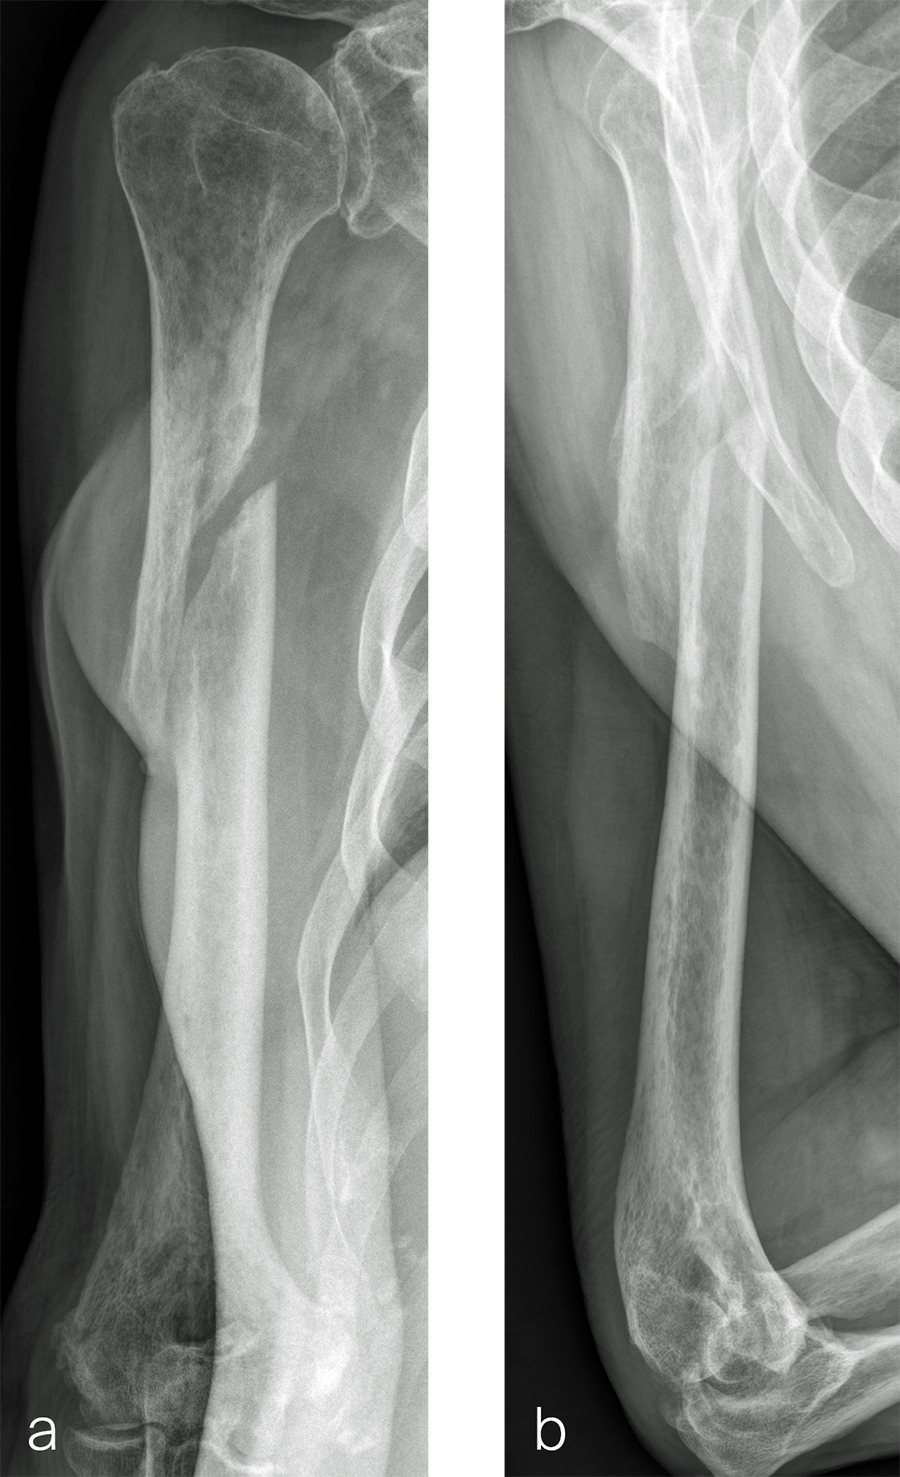

The patient was an 83-year-old right-hand dominant man who sustained a closed right humeral shaft fracture approximately 10 months before presentation. He was not initially offered surgical care and was treated with functional bracing. The patient has moderate pain but mainly complains of instability and lack of strength in his right arm. He was offered surgical nonunion repair with autogenous iliac crest bone grafting but declined iliac crest harvest. X-rays showed oblique nonunion with resorption and confirmed diagnosis of pseudarthrosis (Fig 7).

After debridement and resection of the pseudarthrosis, we accessed the distal segment of the humeral canal and used a small caliber RIA 2 reamer head to harvest intramedullary bone graft (Fig 8) for final plate fixation (Fig 9).